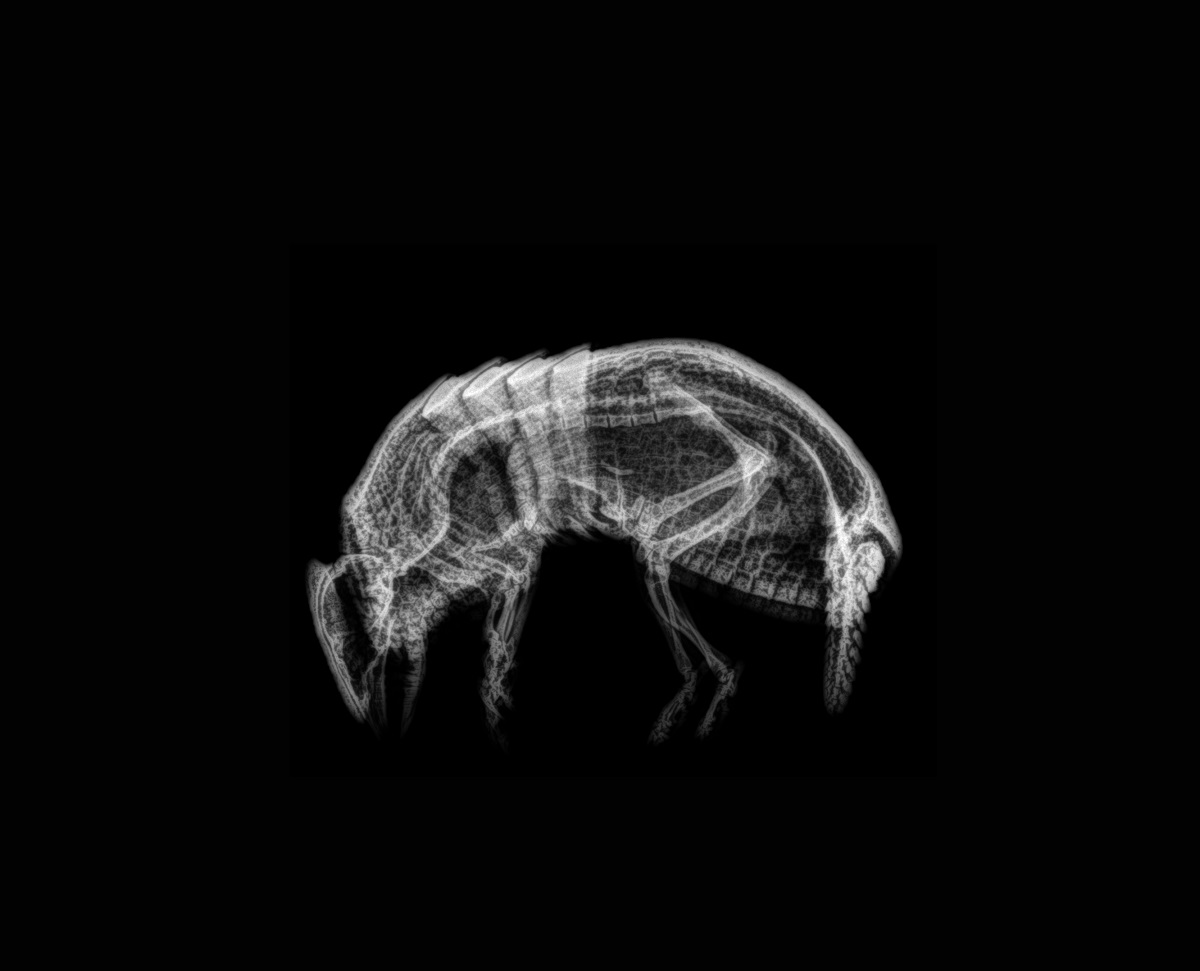

Este procedimiento diagnóstico permite a nuestros expertos brindar una excelente atención médica. Al exponerlos a los rayos X, el equipo puede tomar fotografías de las partes óseas internas de los animales, comprobando la existencia de lesiones o enfermedades que a simple vista no podrían ser identificadas.

Pero, ¿cómo se toma una radiografía de un tigre de Sumatra, de un cálao Gorginegro, un flamenco o un encantador armadillo de tres bandas?

Sin embargo, otros animales no necesitan de esta inmovilización química para hacerles radiografías, es el caso de los armadillos. Con ellos basta con un manejo físico y una buena parte de colaboración voluntaria por su parte. “En ocasiones nos valemos de un proceso de entrenamiento previo que llamamos ‘entrenamiento médico’, en el que el animal recibe una recompensa si nos permite realizar estos estudios de manera voluntaria, sin sujeción física y sin anestesia”.